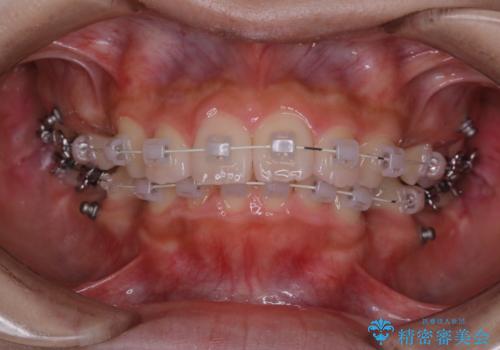

ワイヤー矯正を初めてから2カ月 歯磨き指導とPMTC

- ワイヤー矯正が開始して2カ月が経過しました。まだなかなか歯磨きが上手に出来ないのため、クリーニンングを希望されました。PMTC30分コースと歯磨き指導を行いました。

ワイヤー矯正中はブラッシングが難しくなるため、磨き残しが多くなることがあります。適切な道具を使って、適切なブラッシング方法を習得することで、磨き残しを減らすことができます。

矯正治療中も清潔な口腔内を保つことは、とても大切です。そのため、定期的に専門的な機械・材料を使用したProfessinnalcleaning(pmtc)を行うことがおススメです。